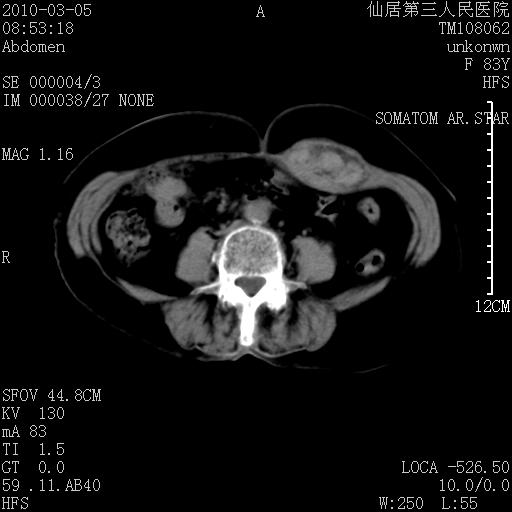

标题: CT24879:腹直肌病变。在线等。 [打印本页]

标题: CT24879:腹直肌病变。在线等。

女性,83y,腹痛一周。

考虑:左侧腹直肌神经纤维瘤可能

神经纤维瘤—伴有出血?

有无外伤,血肿或韧带样瘤

考虑左侧腹直肌血肿,肿瘤性病变待排。

增强看看,mfh可能性大,次之可考虑血肿、bfh、转移瘤、神经纤维瘤、侵袭性韧带样纤维瘤等。肝内钙化灶,右肾结石。

支持血肿

支持腹壁纤维肉瘤

血肿,纤维瘤,子宫内膜异位都有可能。